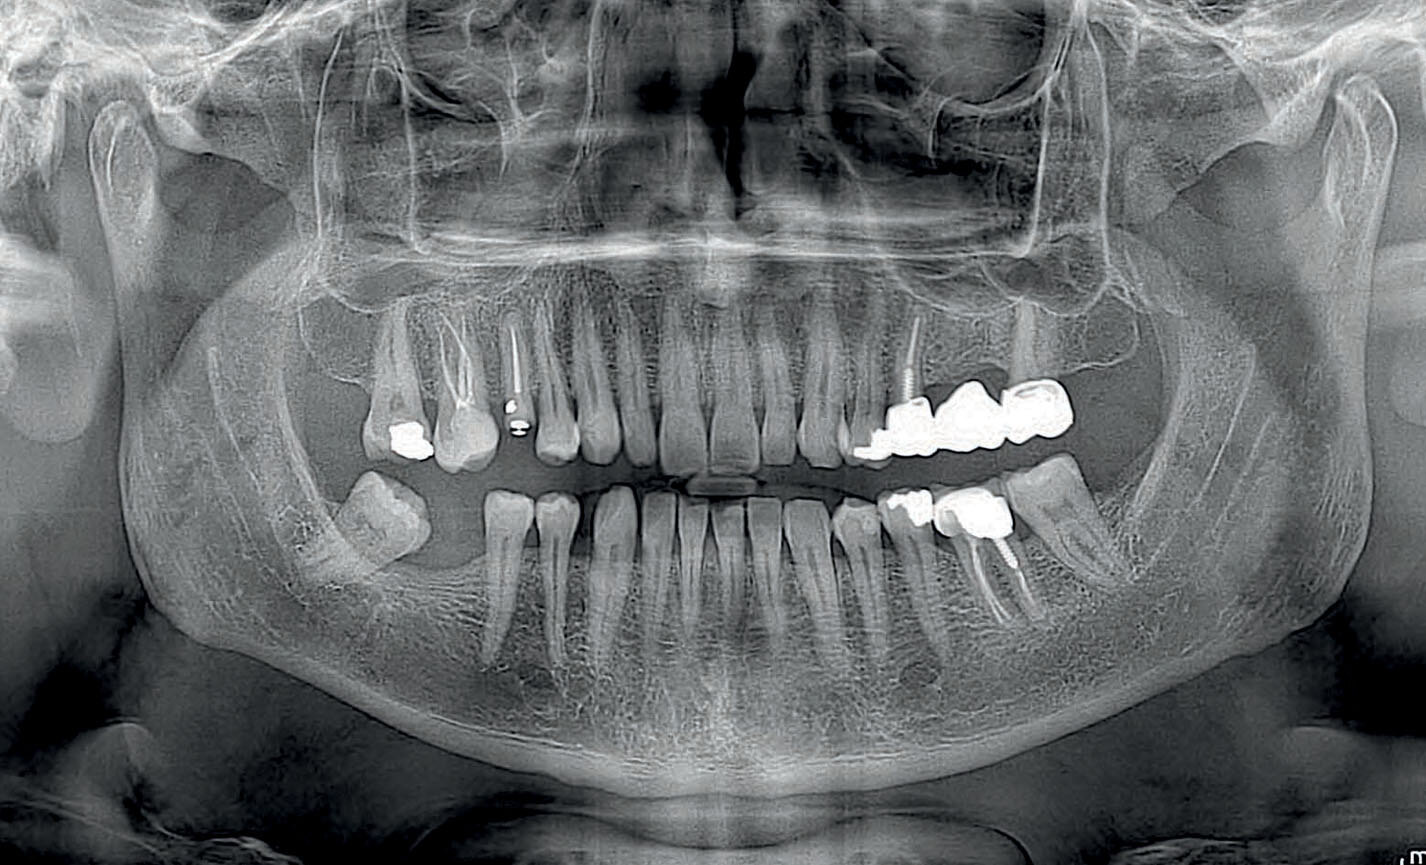

Orthopanoramiques

Panoramique orthogonal : minimise les superpositions d’éléments dentaires adjacents pour une meilleure analyse parodontale.